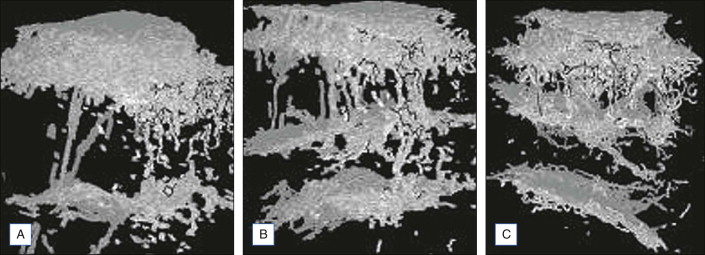

Querleux et al. revealed three principal orientations of the septa: perpendicular, parallel, and angulated at about 45° ( Figs 12.3 and 12.4 ). Women with cellulite had a higher percentage of perpendicular septa than unaffected women (p < 0.001) or men (p < 0.01). For the other two directions, according to presence of cellulite, women with cellulite had a smaller percentage of septa parallel to the skin (p < 0.001) and a higher percentage at 45° (p < 0.001).